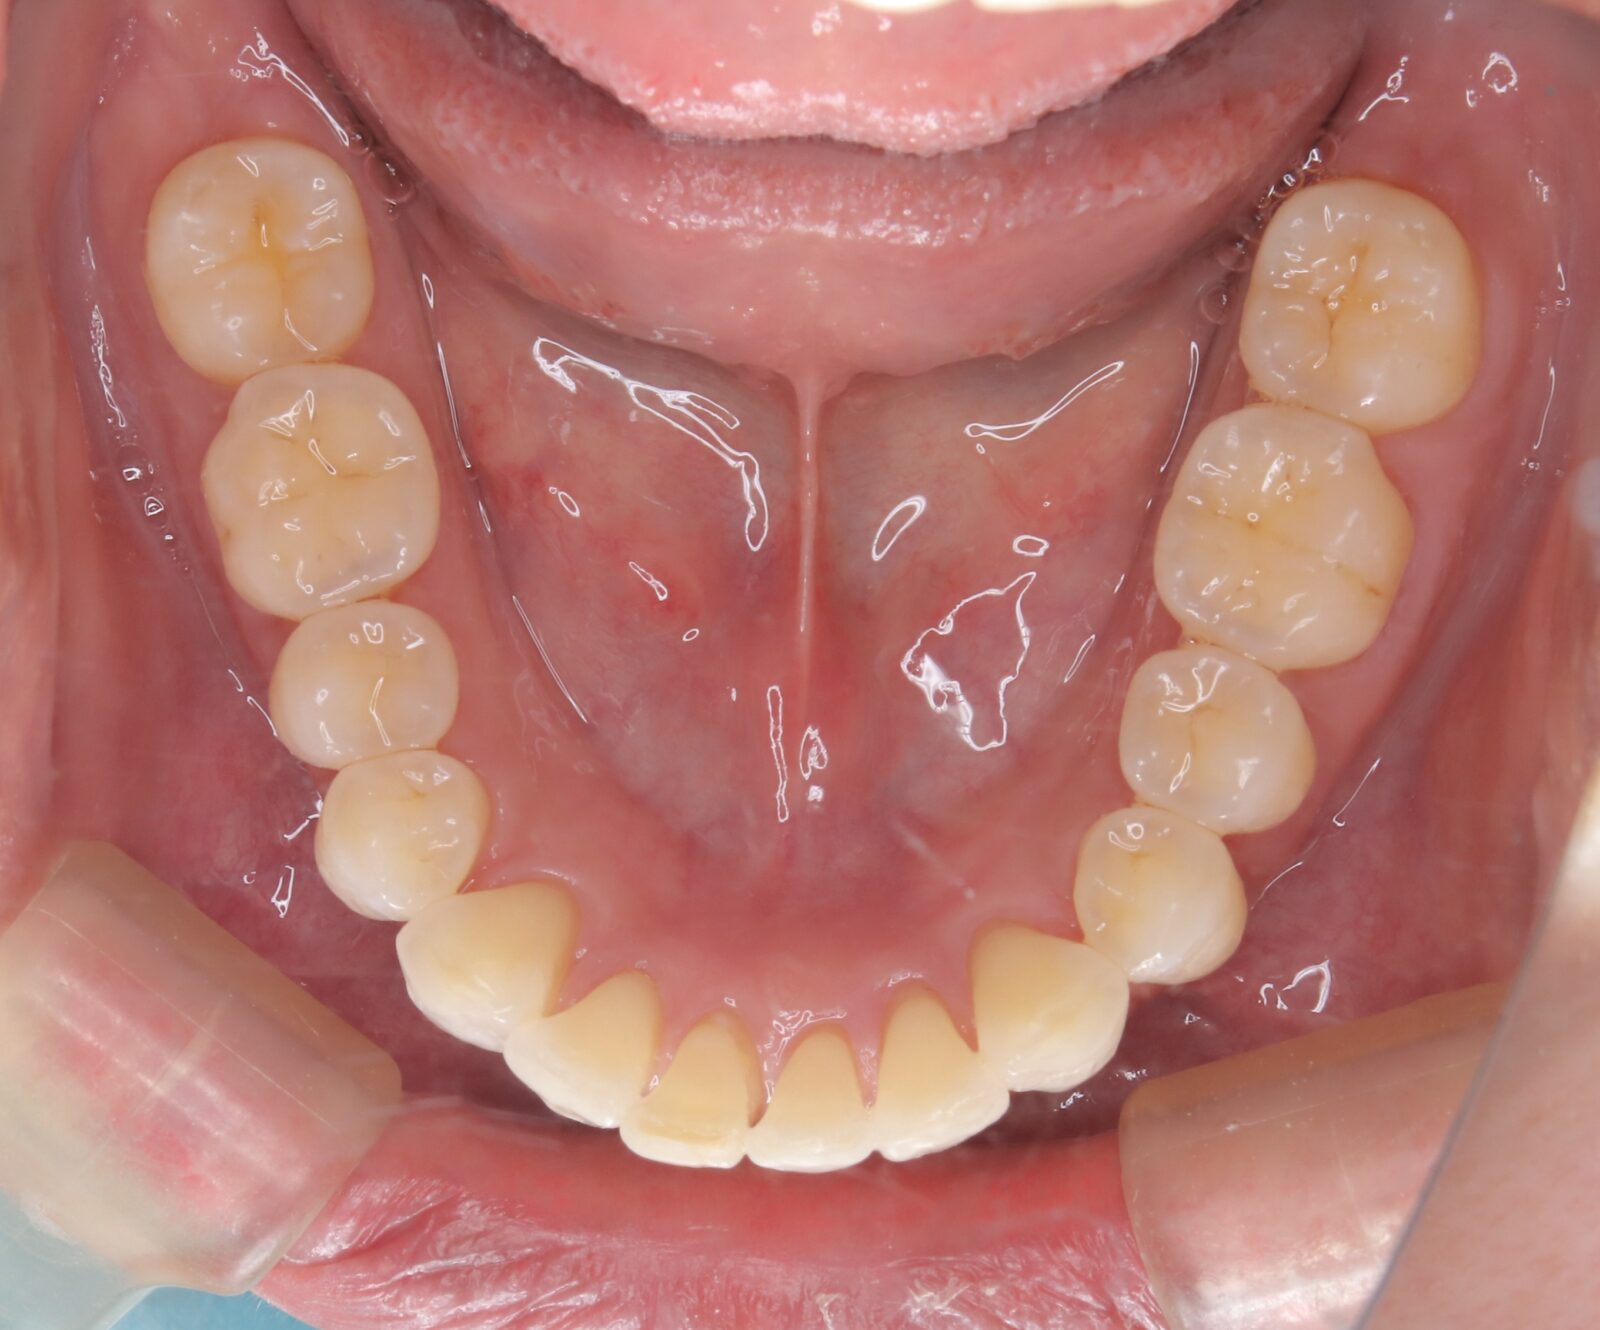

職業柄抜歯をすることができない患者様の症例

職業柄抜歯をすることができないため、小臼歯も親知らずも非抜歯の矯正となりました。 それでは歯を並べるためのスペースを確保できない。歯根の形状を分析し、可能な限り歯冠修復で前歯のサイズを小さくして、歯を動かすためのスペースを作り矯正をスタートした。 下顎前歯歯並びきれないこと、理想的な噛み合わせの獲得は難しいことをご理解いただき治療スタートした。 終了時に初期時の不自由がないことを確認済み。